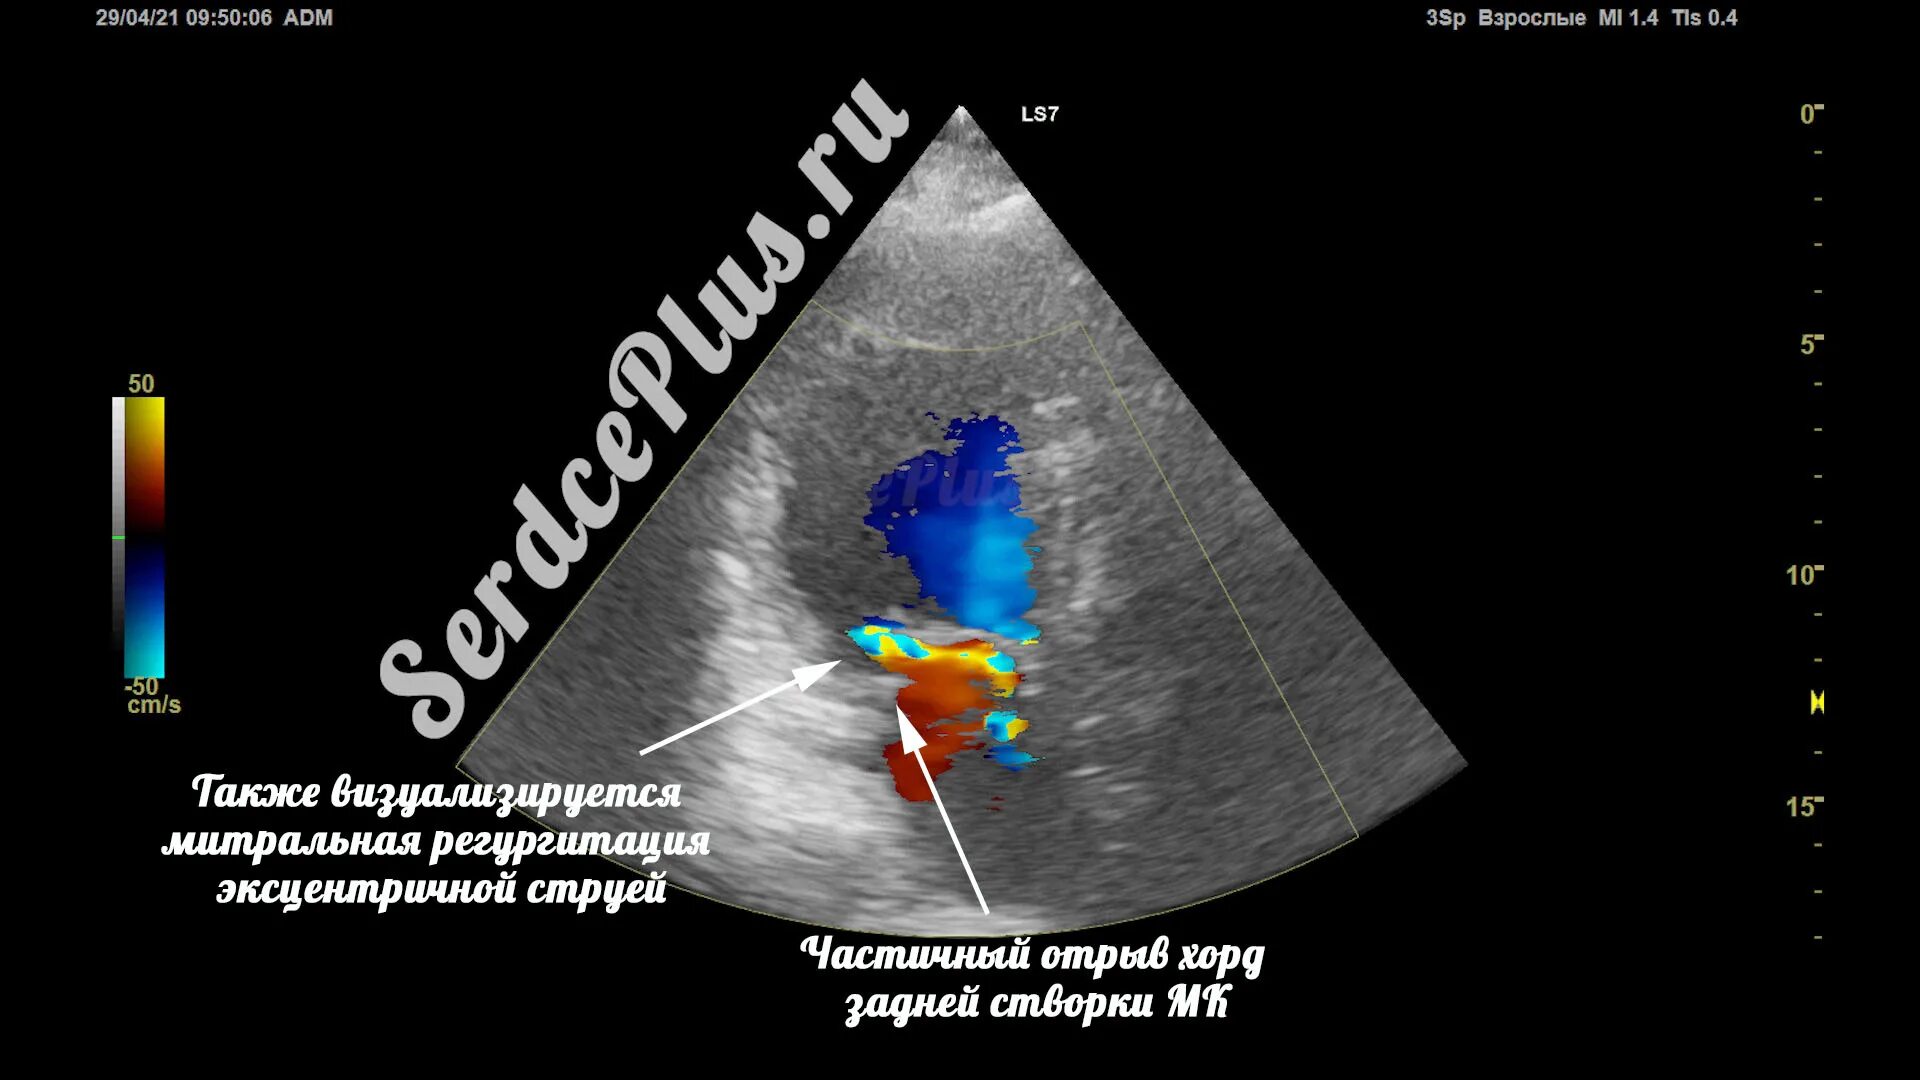

Частичный отрыв